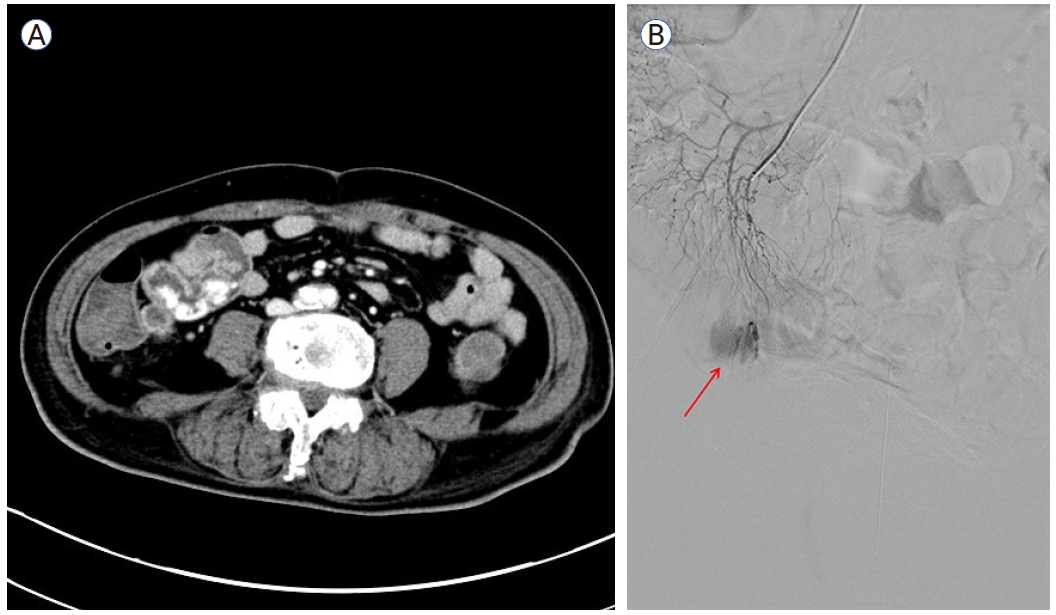

혈관조영술 상에서 회장동맥(Ileal branch)으로부터 혈관 외 유출(extravasation)이 관찰되었고 색전술을 시도하였으나 원발 부위로 의심되는 직혈관(vasa recta)의 굵기가 가늘어 미세 카테터 진입이 실패하였다. 출혈점에 인접하여 최대한 원위부 혈관을 정밀 선택(superselection)한 후 2 mm-3 cm 코일 2개를 사용하여 색전술을 시행하였고(Fig. 2) control digital subtraction angiography 상 에서 혈관 외 유 출이 확인되지 않아 시술을 종료하였다.

Figure 2.

(A) Arrows indicate the ileal branch of the superior mesenteric artery. (B) Embolization microcoil within the ileal arterial branch.

다음날 오후 추가로 혈변이 있어 다시 수혈 후 복부 출혈 CT와 혈관조영술을 재시행하였다. 이 검사에서 이전 코일 색전술이 시행된 부위의 원위부에서 동맥궁(arterial arcades)을 통한 측부 혈관 흐름(collateral flow)으로 인한 것으로 보이는 혈관 외 유출이 관찰되었다(Fig. 3). 원위 회장동맥에 색전술을 수차례 시도하였으나 근위부 동맥에 색전술 시행 시 소장 괴사 가능성이 있어 중단하였고 이후 경과 관찰 중 혈압이 70/50 mmHg까지 떨어지는 등 지속적인 장출혈이 의심되어 수술적 절제를 진행하였다.

Figure 3.

Despite the in situ coil within the superior mesenteric artery, collateral blood flow to the distal branch resulted in rebleeding (red arrow).